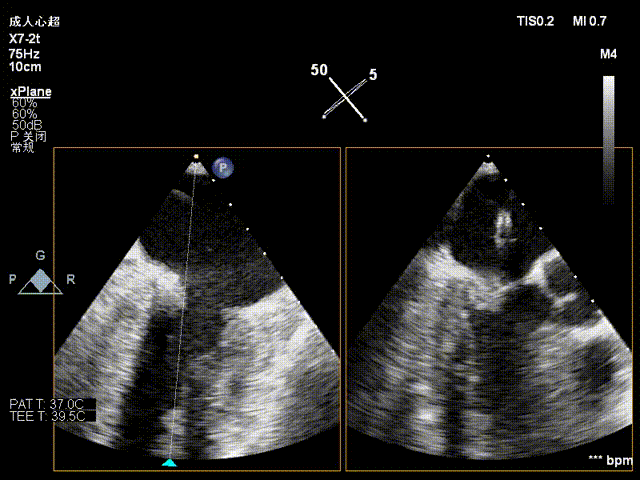

夹合器调整

夹合术后反流评估

检查示组织桥明显,夹合器稳定,残余反流明显减少,降低至1+等级,二尖瓣平均跨瓣压差为3mmHg,经团队评估,手术效果达既定预期,各项指标平稳,顺利结束手术。